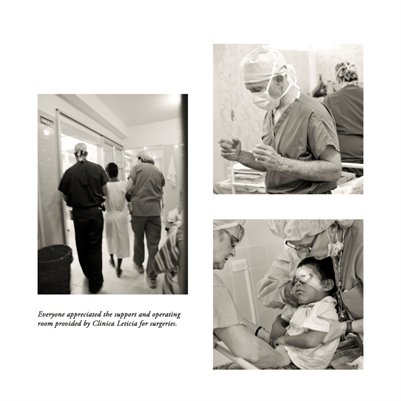

Darkness into the Light. In 2012, The Amazon Project gave eye care to nearly 6000 patients within a 200 kilometer radius of their base in Leticia, Colombia.